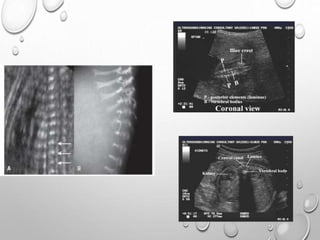

MACROCRANIA

MICROMELIA….SHORT CUBOID BONES AND METAPHYSEAL

SCALLOPING

DECREASED THORACIC CIRCUMFERENCE AND TRUNK LENGTH

DECREASED MINERALIZATION – COMPLETE OR PARTIAL LACK

OF OSSIFICATION OF CALVARIUM ( TYPE 1 ) , SACRAL AND

PUBIC BONES ,VERTEBRAL BOODIES.

PREDOMINANT DEMINERALIZATION OF VERTEBRAL BODIES

WITH ONLY TWO ECHOGENIC POSTERIOR ELEMENTS